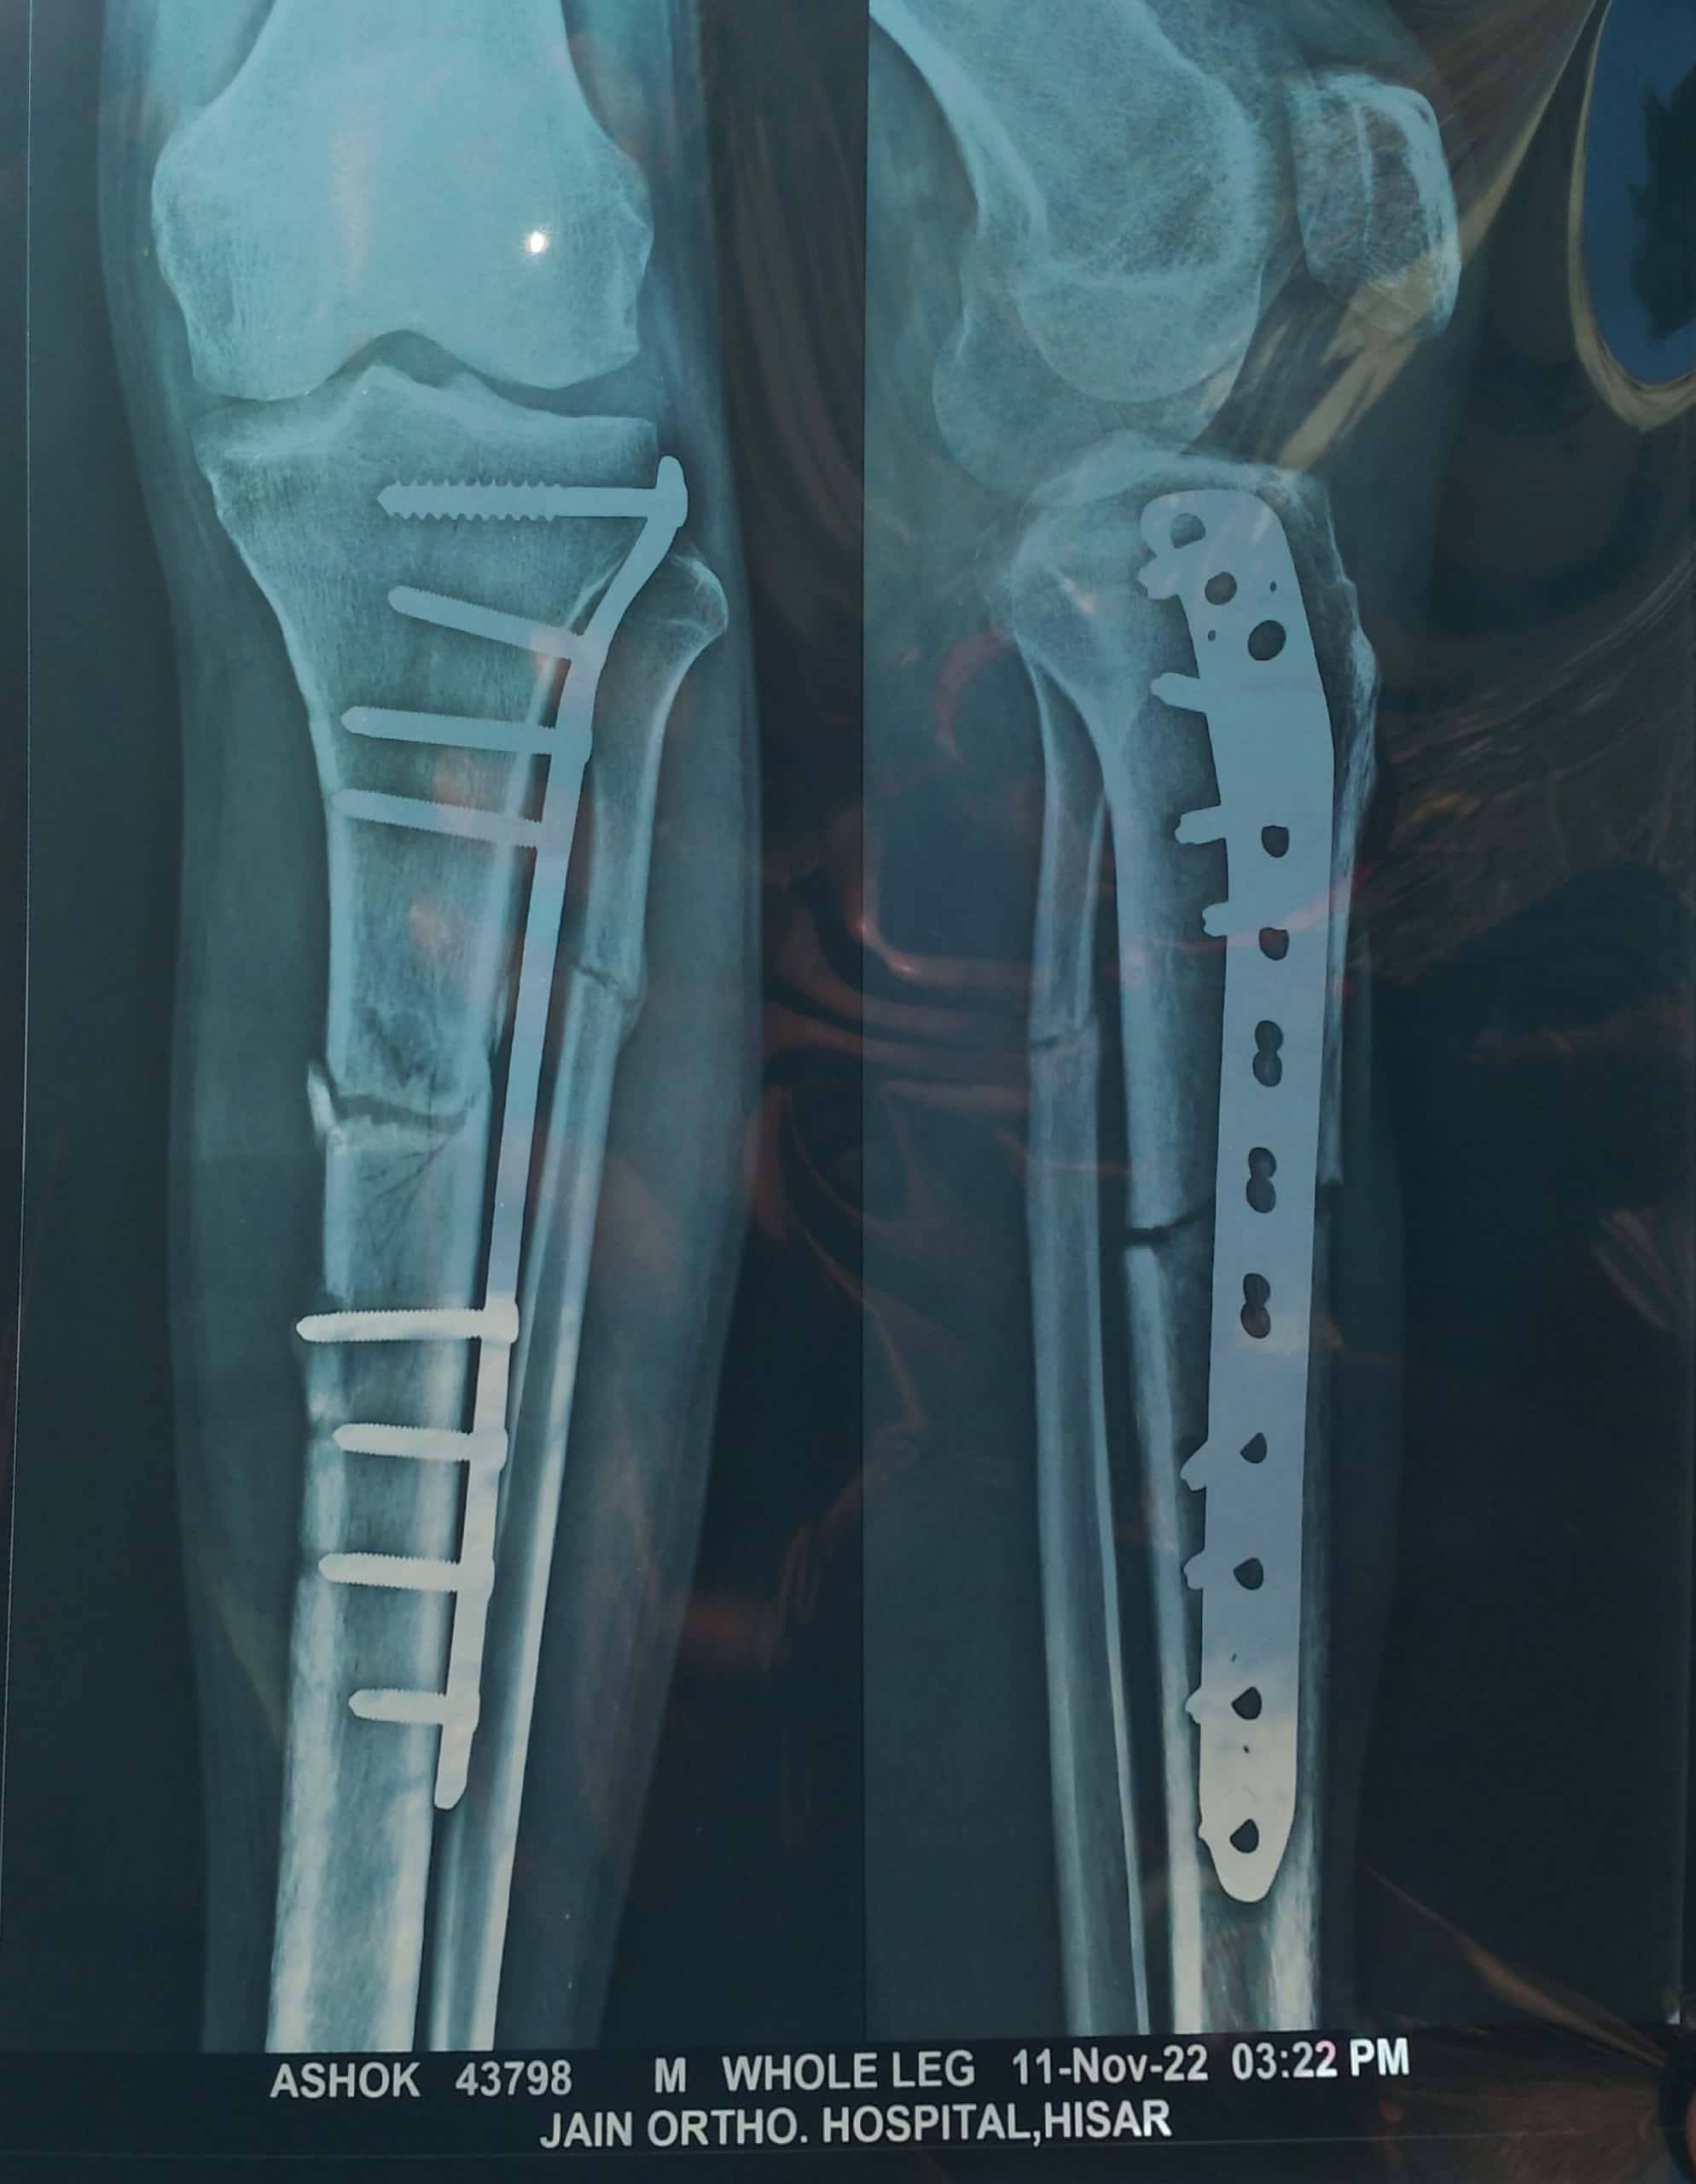

Its has been more than 4 months after my surgery was done for removal of GCT from right distal femur region of my right knee. I am able to bend my legs till 120 degrees but the movement is stil not free the bending starts from 105 degrees and goes upto 120 degrees as i do more repetition. Also in extension i have a lag of 20 degrees i can extend my legs till 160 degrees actively and passively i can do till 180. I am continuing with my physiotheraphy excercise regularly.

Kindly let me know the next steps and any timeline by which i should achieve full movement both in extension and flexion.

you can do physiotherapy and if not possible we can bend it with knee arthroscopy.